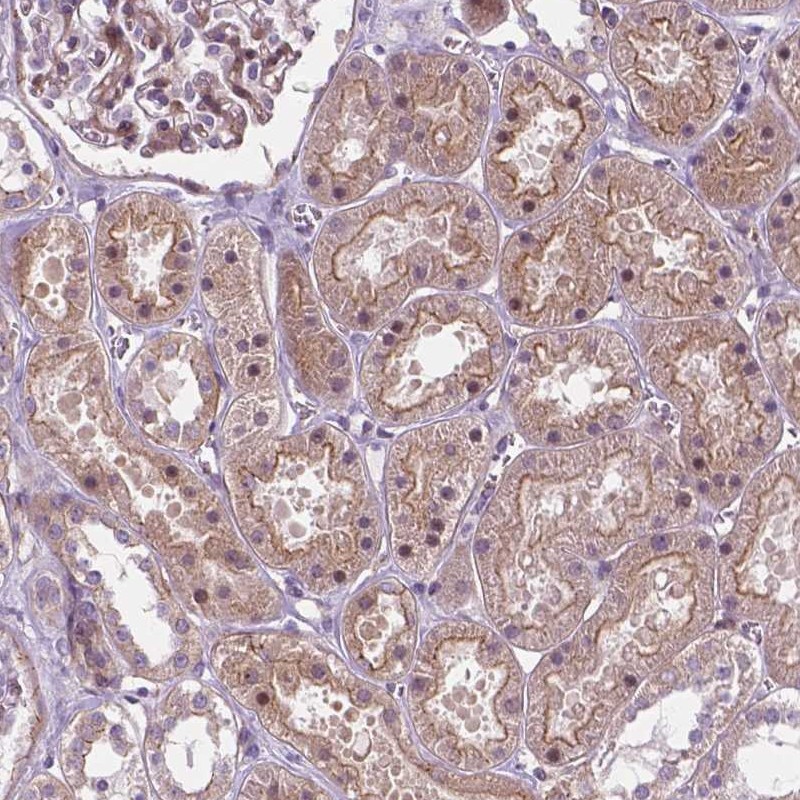

Immunohistochemical staining of human kidney shows moderate membranous and cytoplasmic positivity in cells in tubules.